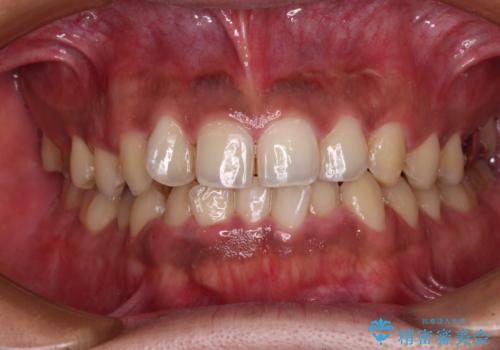

- 前歯のデコボコを気にして来院された患者様です。

前歯が90度近く捻れていたため、しっかりと治すことを考えるとワイヤー矯正の方がおすすめではありましたが、本人の希望によりインビザラインを用いて矯正治療を行うこととしました。

インビザラインは、十分な装着時間が達成されると前歯のデコボコをしっかりと改善できますが、1日の装着時間が20時間に達しなくなると、不十分な仕上がりとなるため、しっかりと装着するよう指示をしました。

途中2年強の来院がなく、改善されていたデコボコが元に戻ったり、装着時間が不足しており前歯のデコボコは十分に改善することはできませんでしたが、5年間の有効期限内で可能な限り歯列を整えることができました。